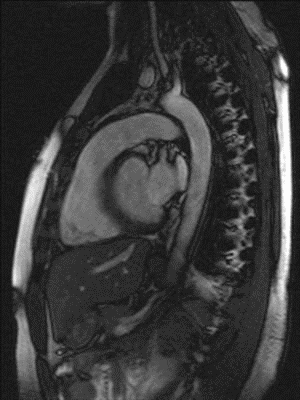

MIR Showing the Heart Pumping